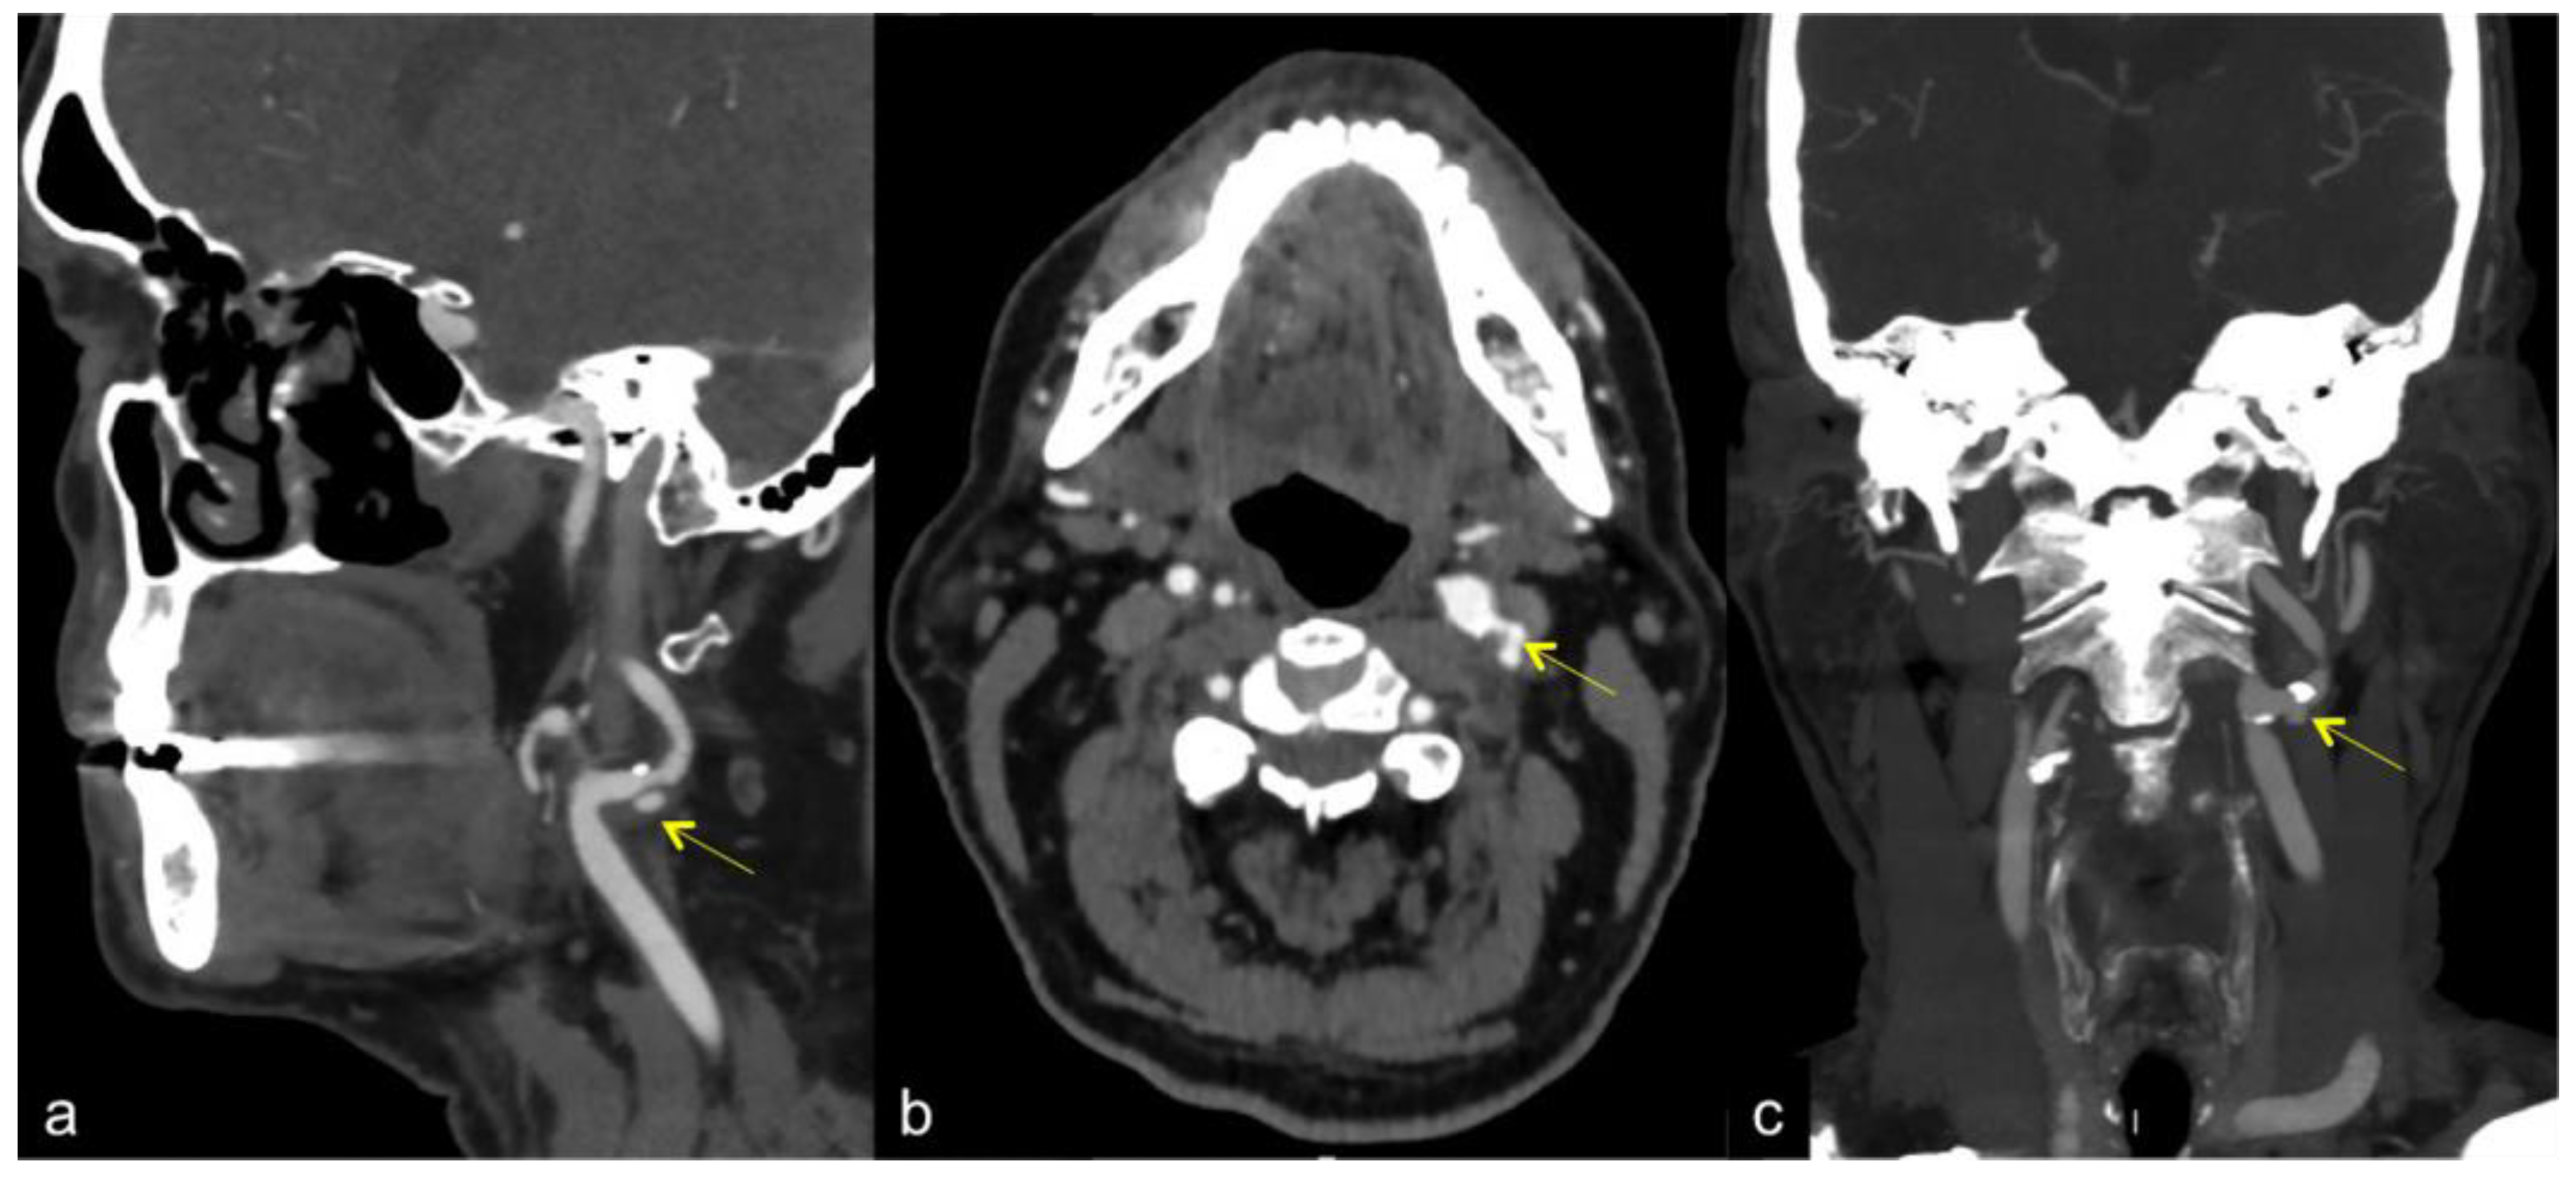

- Fresilli, D.; Di Leo, N.; Martinelli, O.; Di Marzo, L.; Pacini, P.; Dolcetti, V.; Del Gaudio, G.; Canni, F.; Ricci, L.I.; De Vito, C.; et al. 3D-Arterial analysis software and CEUS in the assessment of severity and vulnerability of carotid atherosclerotic plaque: A comparison with CTA and histopathology. Radiol. Med. 2022, 127, 1254–1269. [Google Scholar] [CrossRef] [PubMed]

- Sultan, S.R.; Bashmail, F.T.; Alzahrani, N.A.; Alharbi, S.I.; Anbar, R.; Alkharaiji, M. Is 3D ultrasound reliable for the evaluation of carotid disease? A systematic review and meta-analysis. Med. Ultrason. 2022; online ahead of print. [Google Scholar] [CrossRef]

- Johri, A.M.; Nambi, V.; Naqvi, T.Z.; Feinstein, S.B.; Kim, E.S.H.; Park, M.M.; Becher, H.; Sillesen, H. Recommendations for the Assessment of Carotid Arterial Plaque by Ultrasound for the Characterization of Atherosclerosis and Evaluation of Cardiovascular Risk: From the American Society of Echocardiography. J. Am. Soc. Echocardiogr. 2020, 33, 917–933. [Google Scholar] [CrossRef]